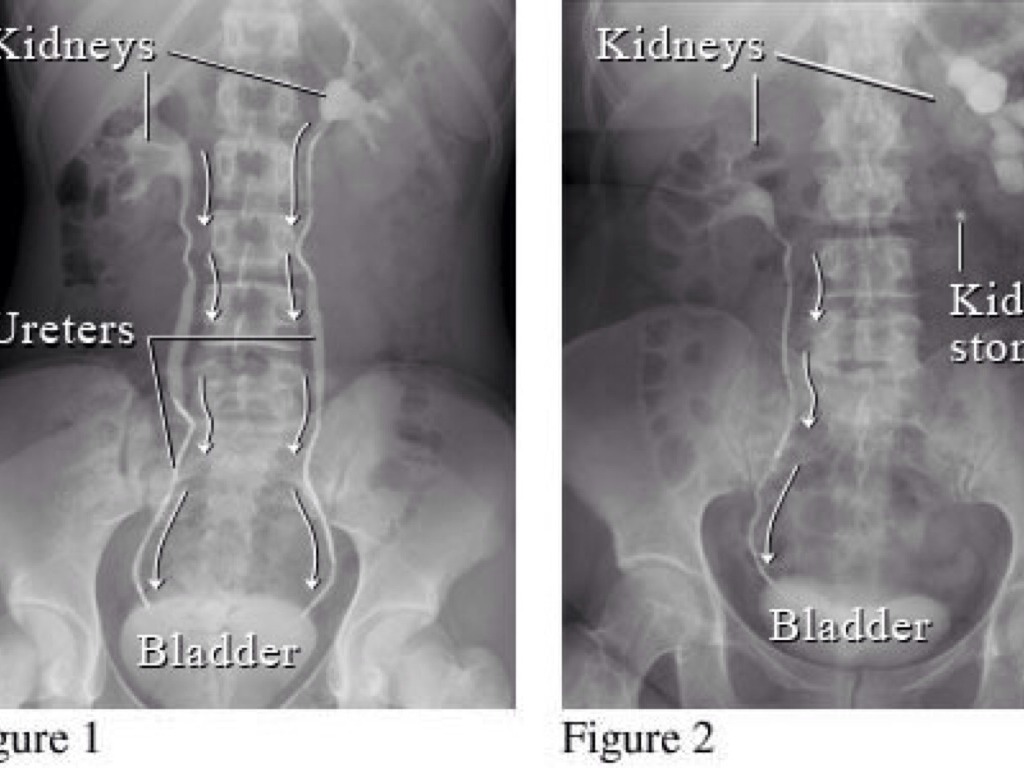

WHAT DID I SWALLOW?